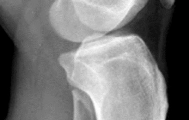

A 5-year-old boy falls from monkey bars and sustains a widely displaced supracondylar humerus fracture. Upon presentation to the emergency department, the hand is pink but the radial pulse is absent. He undergoes prompt closed reduction and percutaneous pinning. Post-operatively in the recovery room, the radial pulse remains absent, but the hand is warm with brisk capillary refill (less than 2 seconds) and normal oxygen saturation on the index finger. Which of the following is the most appropriate next step in management?

Correct Answer: Observation with close neurovascular monitoring

The patient has a 'pink, pulseless' hand following reduction and pinning of a supracondylar humerus fracture. Current pediatric orthopedic guidelines recommend observation for a well-perfused (pink, warm, brisk capillary refill) but pulseless hand post-reduction. The collateral circulation around the elbow is robust enough to maintain distal viability. Vascular exploration is indicated if the hand is white, cold, and poorly perfused (pulseless and ischemic) after a well-aligned reduction. Arteriography is generally not indicated and delays treatment if the limb is ischemic. Removing pins would destabilize the fracture and risk further neurovascular injury.